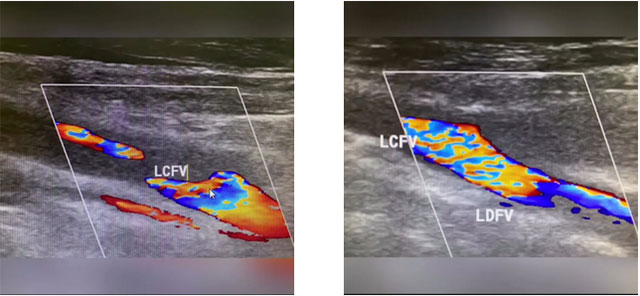

患者為56歲男性,患有高血壓。入院時,腦出血術后,顱內靜脈竇血栓術后,左側肢體活動不利,左側上肢肌力1級,下肢肌力1級。下肢彩超顯示,久坐后左側股總靜脈、股淺靜脈、股神靜脈血栓形成,左側腘靜脈血流淤滯,CTA提示右下肺動脈下段栓塞。如不及時采取措施,血栓可能會進入患者肺部引起肺栓塞,從而危及生命。

▲ 彩超顯示下肢深靜脈血栓形成